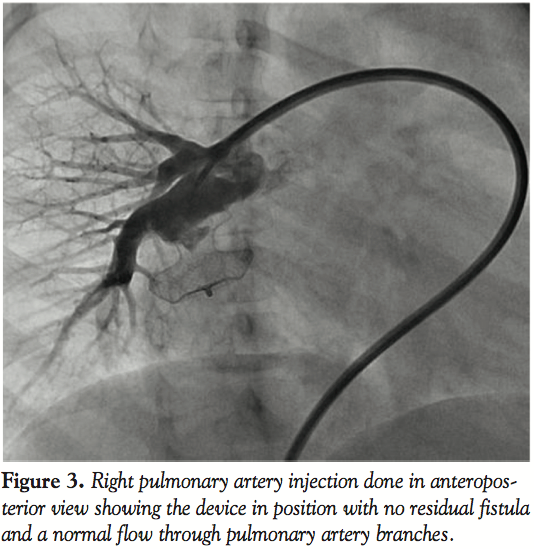

We did the procedure under conscious sedation. The femoral artery and veins were percutaneously cannulated. Unfractionated heparin (100 units/kg) was administered after vascular access was obtained. A 5 French (Fr) multipurpose catheter with 0.035″Terumo wire was introduced from femoral vein, inferior vena cava, right atrium, right ventricle, main pulmonary artery to RPA. Right pulmonary artery angiography performed in anteroposterior view showed a large feeding artery from distal, prebranching portion of RPA communicating

with a large aneurysmal sac of the left atrium (Figure 1, Video 1). The fistula was crossed with the multipurpose catheter and 0.035-inch Terumo wire and this was exchanged with 0.035-inch Amplatz extrastiff exchange length wire that was parked with a good loop in the left atrium. We introduced a 24 mm AGA sizing balloon to occlude the vessel, rule out additional fistula, and to measure the narrowest portion of the feeder as it entered the left atrium (Figure 2, Video 2). The communication was

single and the narrow segment measured 14 mm with the proximal portion measuring 26 mm. Considering the morphology of the fistula, we decided to close the defect antegradely. As the fistula was large and roomy we decided to close the feeding vessel with an atrial septal occluder. The left atrial disc would easily be accommodated in the aneurysmal sac and the right atrial disc was expected to configure into the shape of the feeding artery without protruding into the lumen of RPA. The constricted segment was well away from the branches of the RPA as well as the opening of the pulmonary veins into the left atrium. The balloon was removed and an 8 Fr long Cook sheath was introduced antegradely over the Amplatz wire through RPA, across the fistula into the LA. As the constricted segment measured 14 mm, we deployed a 16 mm Cardiofix atrial septal occluder (Starway Medical Corporation) across the narrow portion of the feeding vessel. While the left atrial disc assumed the expected shape, the right atrial disc was rounded due to comparatively less space in the feeding artery. We did RPA injections in multiple views to be sure that there was no obstruction to RPA flow as well as that there is no residual flow across the fistula (Figure 3, Video 3). After checking the stability of the device, it was released (Figure 4, Video 4). The patient’s saturation improved to 100% and there was no residual fistula on follow-up. He was put on oral aspirin for 6 months and is doing well on follow-up without any complications.